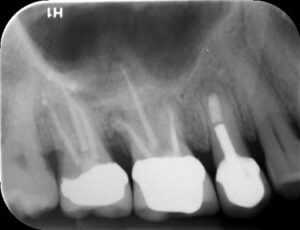

Before and Afters

The tooth will be examined and an x-ray will be taken, a local anaesthetic will be administered. An opening will be made in the crown of the tooth and small instruments will be used to clean the canals. Once the canals have been cleaned and shaped, they will be filled with a polyester synthetic root canal filling and sealer. To make your Root Canal Treatment successful at Notley Dental Care, we will use a dental microscope with magnification so that we get a better view.

Yes, the tooth will require a permanent restoration. This could range from a simple filling to a large build-up with posts and pins. The tooth is more brittle after a Root Canal Treatment and therefore is more susceptible to fracture. If the filling is large, the tooth may need a crown as well. A crown protects the tooth from breaking.